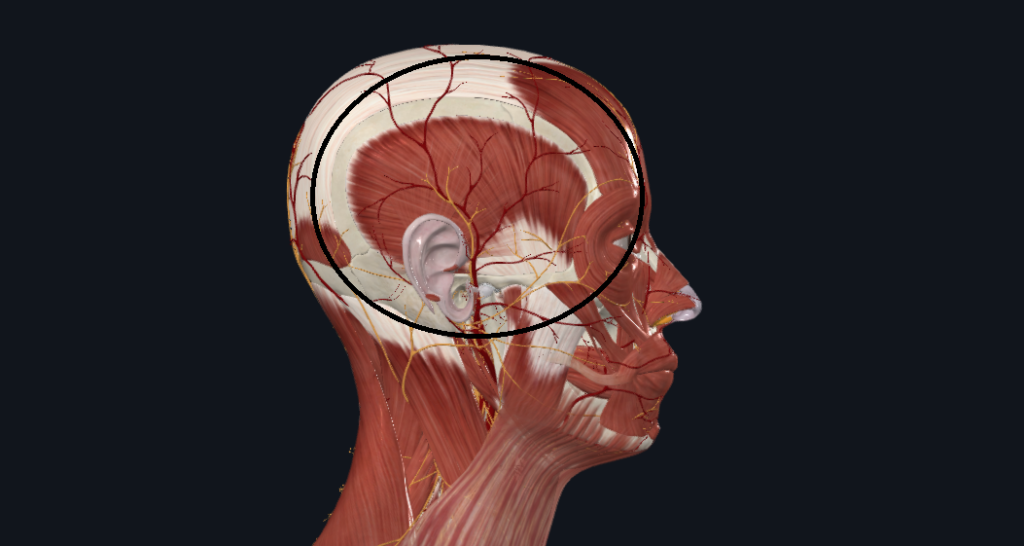

その姿勢では奥歯が噛み合いやすくなり、 さらに首の前の筋肉・咬筋・側頭筋が緊張 → 食いしばりが助長される という悪循環に陥ります。

特に側頭筋(こめかみにある筋肉)は、

- こめかみを走る神経(三叉神経の枝)

- 血管(浅側頭動脈)

を圧迫するため、側頭部(こめかみ)の頭痛を引き起こすこともあります。

※解剖学アプリを使用し、筆者が作成した画像です